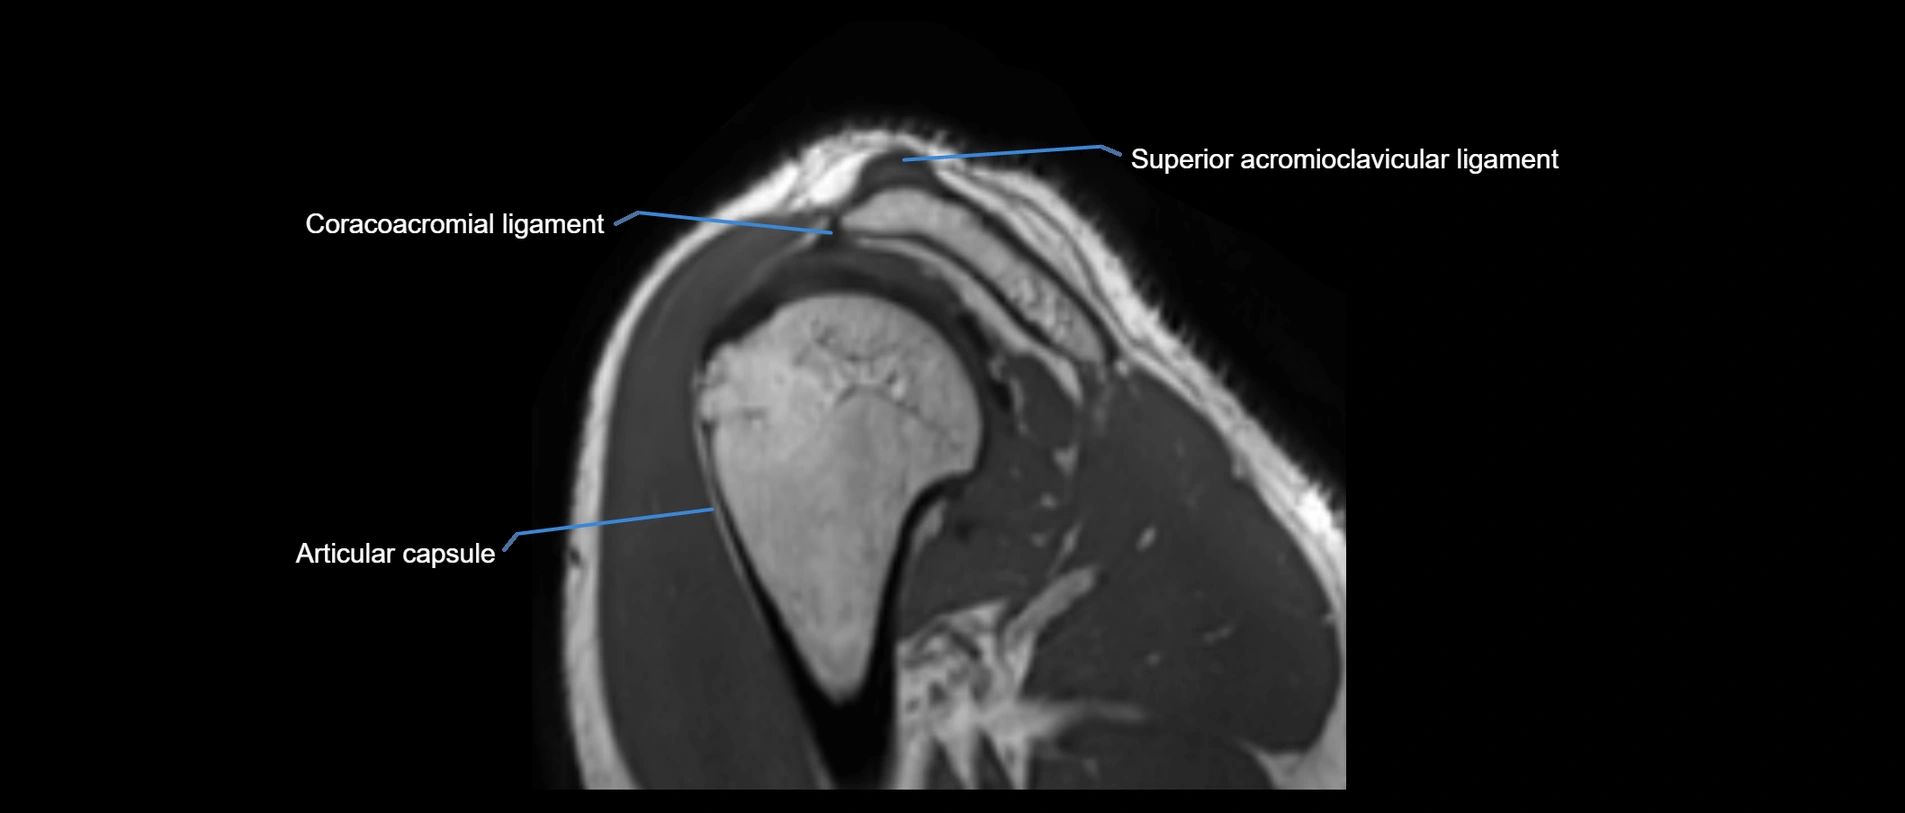

MRI images

image